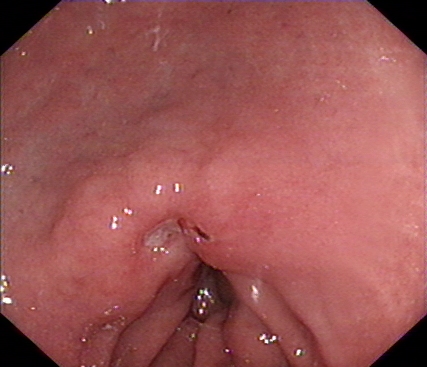

我们再来看一组胃镜图片,由胃溃疡到胃癌的过程(图片来源于网络)。患者未按医生医嘱,定期复查胃镜活检,最后进展为晚期胃癌。

消化内镜是目前发现消化道肿瘤的有效手段。胃肠镜检查通常可发现可疑病变,进一步行精查内镜,通过图像增强内镜(电子染色或染料染色内镜)、结合放大等加以观察分析,判断病变的性质、边界范围判定、分化程度及浸润深度,不仅大大提高了早期消化道癌的检出率,并且可以评估病变是否适合内镜下治疗。内镜微创治疗,内镜下粘膜切除术(EMR)、内镜下粘膜剥离术(ESD)等是切除早期癌变组织,实现临床治愈的有效方法。